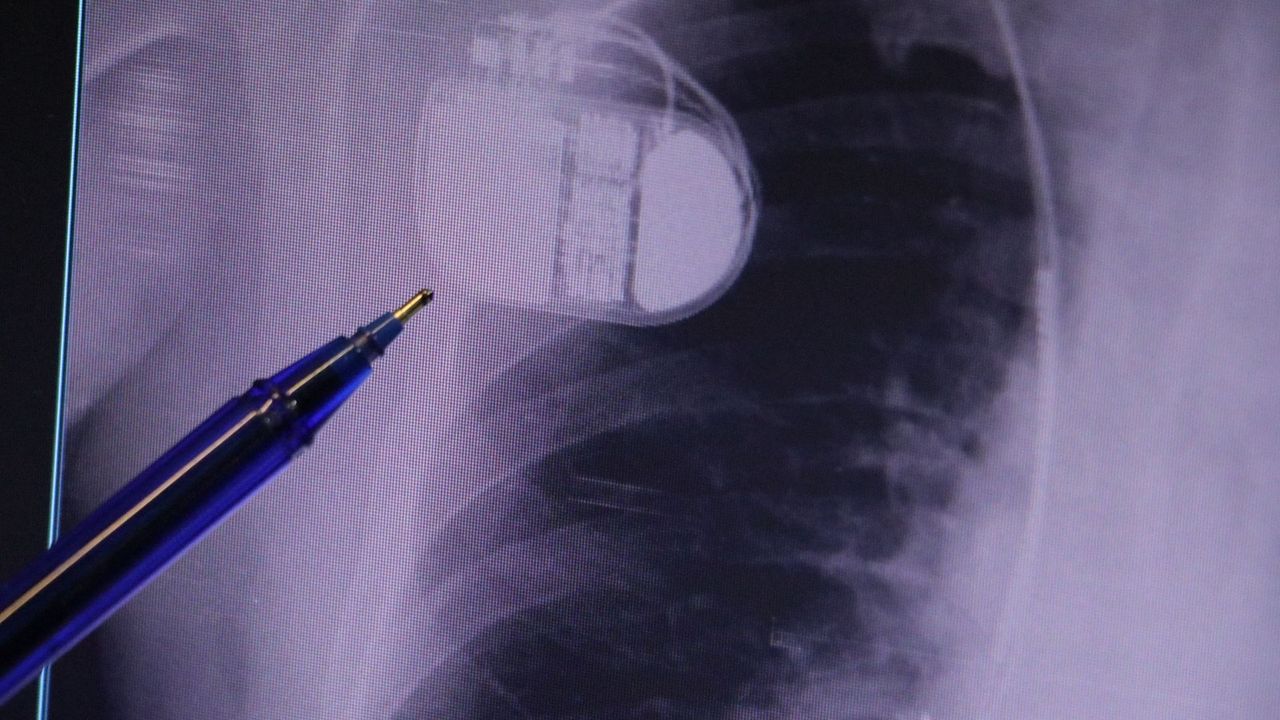

Kalp krizleri sonrası kalp dokusunun zarar gördüğünü söyleyen İsmail Erdoğu, "Dünyada artık kalp hastalıkları en sık ölüm sebeplerinden biri. Kalp hastalıklarında çok fazla grup var. Biz kalp hastalıkları deyince sadece kalbinde stent olan ve damarlarında sorun bulunan insanlardan bahsetmiyoruz. Aynı zamanda tansiyon ve şeker hastaları da kalp hastalıklarına aday. Toplumun yaklaşık yüzde 30-35'lik bir kısmını kapsıyoruz. Çok yaygın bir hastalık ve bu hastalıkta teknolojik kapsamda, ilaç konusunda son 30 yılda çok ciddi gelişmeler oldu. Geçmişte insanları hastanelerde kalp krizinden dolayı kaybederken şimdi hastaneye başvurular sonrasında yaşama tutunmak büyük oranda mümkün. Yaşanan ölümler ise genellikle hastaneye gelmeden önce gerçekleşmekte. Kalp krizinden kurtulmanın hastalarda belli bir bedeli oluyor. Kalp krizi sonrası kalpteki dokular zarar görüyor ve kalp yetersizliği oluşuyor. Bu kalp yetersizliği olan kalplerde ritim bozuklukları ve ani ölümler gibi sorunlar gündeme gelebiliyor. Bunlardan uzun vadede korunmak için hastalarda mutlaka bir kalp piline ihtiyaç duyuluyor" dedi.

Kalp pilleri ile MR cihazına girilebileceğini belirten Erdoğu, "Çok büyük bir ameliyat değil ama yine de ciddi bir cerrahi işlem. Kalp pili, tıpta son 30 yılda yaşanan gelişmelerden en büyüğü. Bir bilgisayarın küçültülüp insan vücuduna konulmuş hali aslında. İnsan ömrünü ciddi oranda uzatan bir tedavi. İnsanlar bir şokla hayata tutunurken, pil olmasaydı öleceğini düşündüğümüz birçok hastamız var. Kalp pilinin bu özelliği, uygun hastalarda ciddi oranda ani ölümü engelliyor. Hastanın başına gelecek bir kalp durması durumunda yanında bir sağlıkçı yoksa, onun ritmini düzeltecek defibrilatör cihazı yoksa hastayı hayatta tutmak mümkün değil. Uygun endikasyonlarda kalp pili olduğu zaman, pil hastaların ritmini algılıyor ve acilde yapılan şoklamayı yaparak hastayı hayata döndürüyor. Kalp pillerinde yeni teknolojilerle MR'a girmek mümkün, tomografiye zaten girebiliyorlar. Tarama cihazlarından geçmelerini uygun görmüyoruz. Bu tarz durumlarda hastalarımız 'kalp pilim var' dediğinde muaf tutuluyorlar. Kalp pilleri ciddi teknolojik cihazlardır. Vücudun içindeki titreşimi, örneğin mikser kullanmak, kolunu sallayacak herhangi bir eylem kalp pilinde olumsuz etki oluşturabilir. Soğuk havalarda vücutta oluşan ciddi titremeler kalp pilinin hafızasını karıştırıp kalbin durduğunu düşündürebilir ve gereksiz şoklama yapabilir. Bu tarz kişilerin soğuk havalarda daha temkinli olması gerekir" diye konuştu.